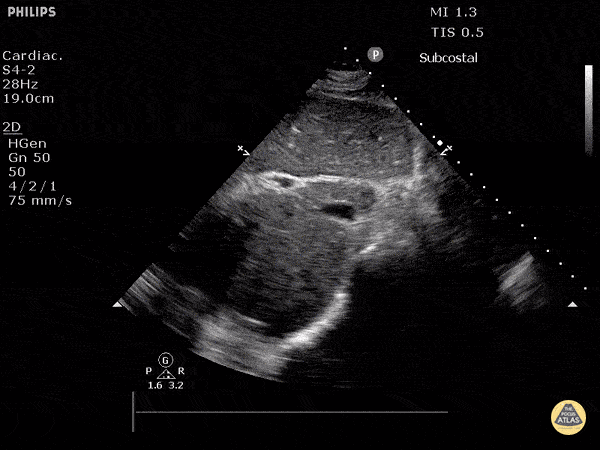

76F Prev Breast CA refer for cellulitis but ED +PCE, cardio for urgent ?tap

Which one are you not concerned about?

What's the pulsus?

IVC and Pericardial Effusion

Evidence: http://pocusjournal.com/article/2016-01-03p12/

Example: http://www.thepocusatlas.com/pericardium

Tutorial: https://web.stanford.edu/group/ccm_echocardio/cgi-bin/mediawiki/index.php/Tamponade

IVC plethora – Dilatation and less than a 50 percent reduction in the diameter of the dilated inferior vena cava (IVC) during inspiration, reflecting a marked elevation in central venous pressure, is frequently seen in patients with cardiac tamponade In one report, IVC plethora was associated with pulsus paradoxus and was present in 92 percent of those with pericardial effusion who required pericardial drainage.

It is highly sensitive but not at all specific for cardiac tamponade